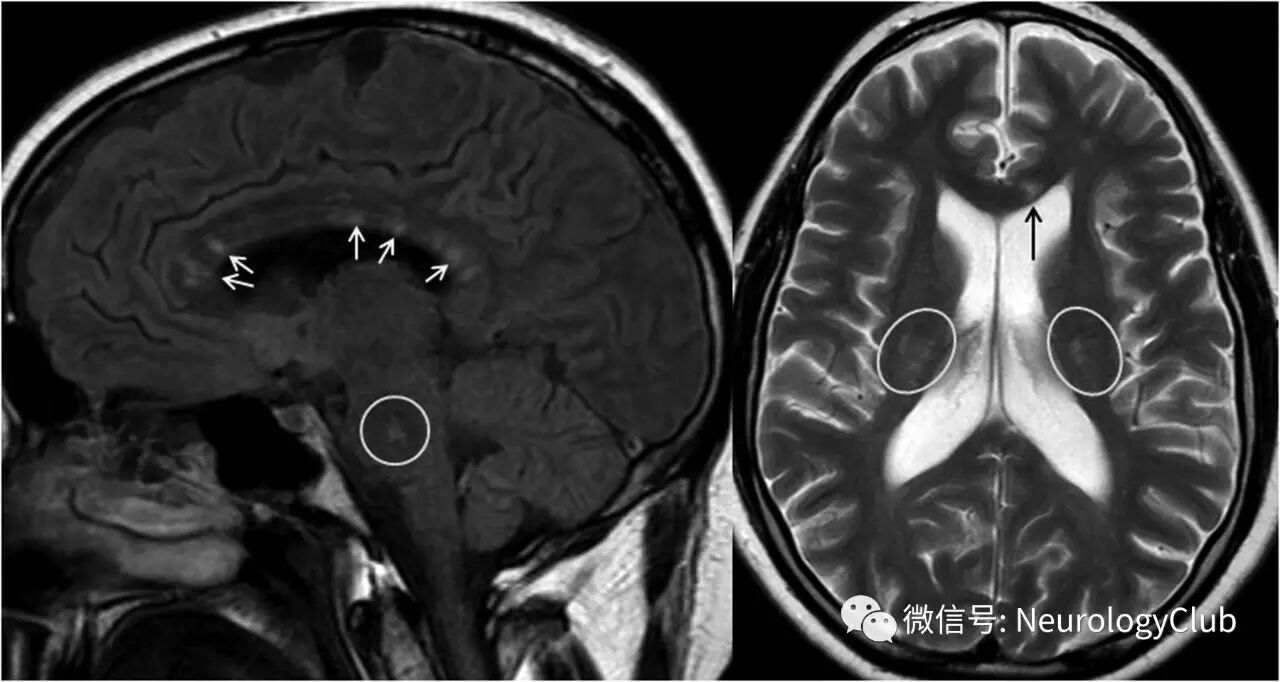

特异性的神经影像学表现,定义为T2/FLAIR像多发圆形病灶,至少需要有一个病灶位于胼胝体(“雪球样”,见图1)。病灶也可表现为不同大小和形状,如矩形、三角形或线形(“条幅状”或“锥状”)。边界清晰的T1低信号病灶,伴或不伴强化,灰质病灶,以及软脑膜强化均支持诊断,但本身无特异性。脑部受累的定义是至少存在一个前述临床表现以及典型的MRI表现。

图1  2例SuS患者的脑部MRI(A)矢状位FLAIR像(胼胝体“雪球样”病灶)和(B)水平位T2